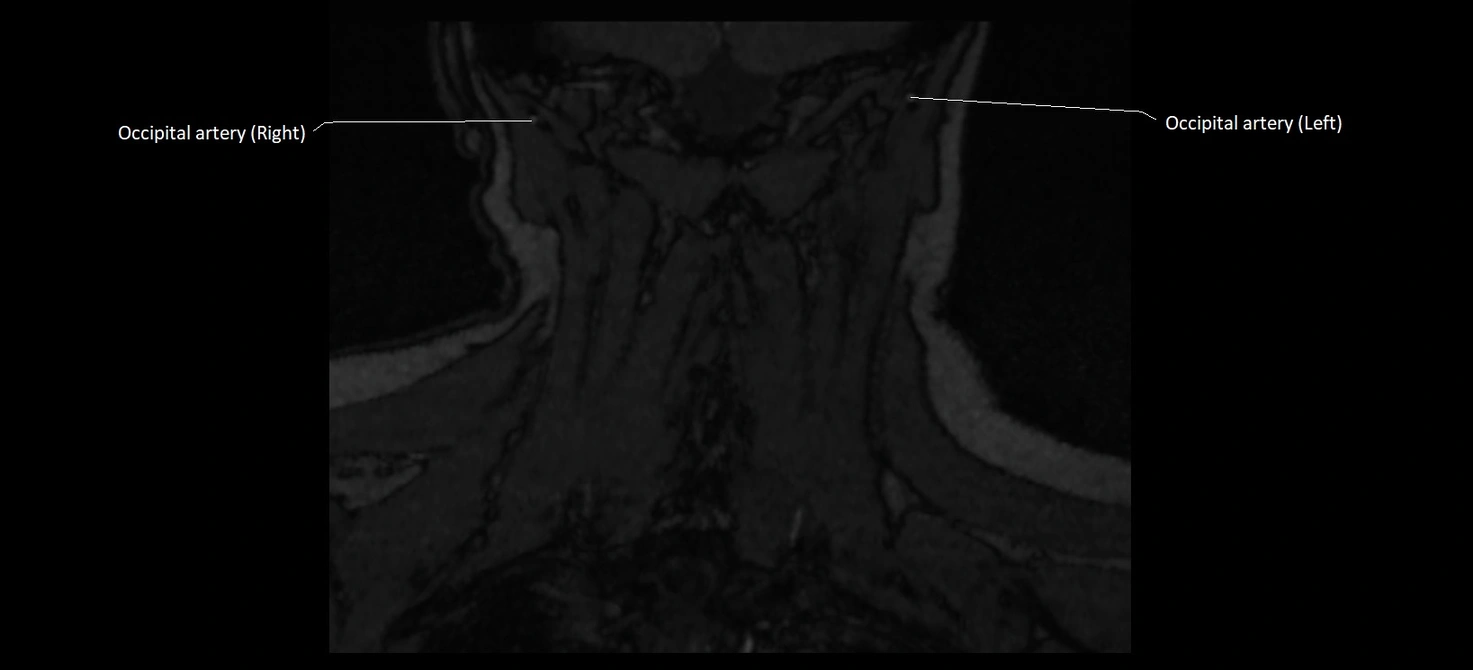

CT image

image